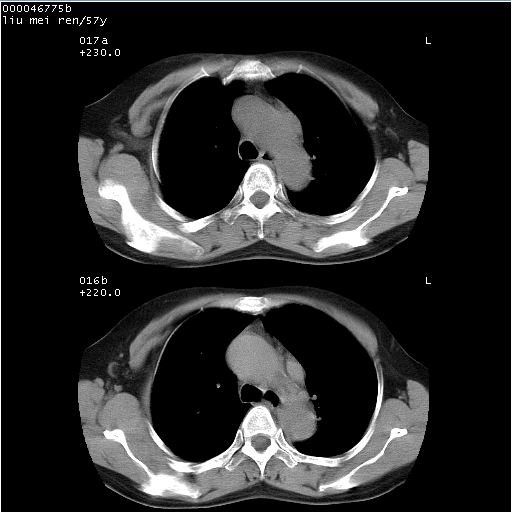

患者 女,57岁。因车祸受伤,其家属要求行“全身ct检查”。平素健康。

胸部ct轴位平扫(层厚10mm,螺距1.5,重建间隔10mm),图像如下:

上腔静脉变异

左位上腔静脉,先天变异。

左位上腔静脉,先天变异。与双侧上腔静脉区别。